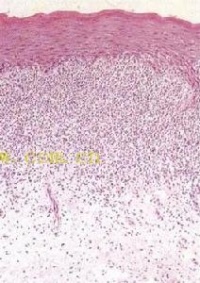

6、组织病理具有特征性。表皮角化过度,颗粒层呈据灶性楔形增厚,棘细胞不规则增厚,表皮突呈锯齿状,基底细胞液化变性,真皮上部淋巴细胞呈带状浸润,真皮乳头层可见胶样小体及嗜黑素细胞。